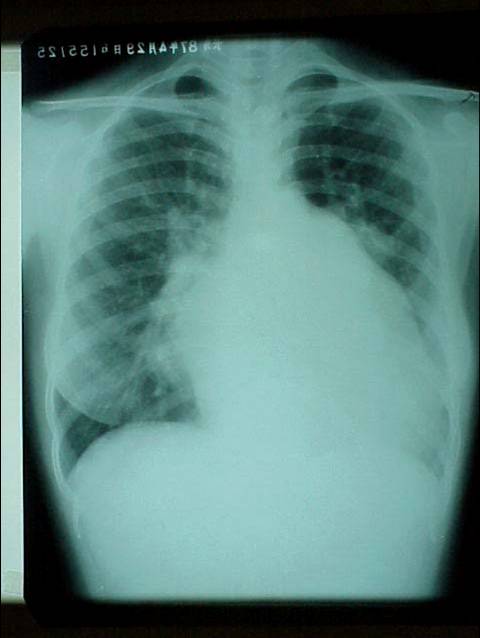

照片名称:大量胸腔积液